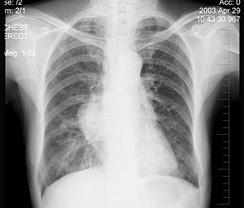

问题 女性,57岁,因胸痛,咳嗽一月就诊,不发热,咳白色痰,无痰中带血,X线检查见图,最可能的诊断是 ( )

选项 A、右肺肿瘤 B、间质性肺疾病 C、右肺炎症 D、纵隔肿瘤 E、右侧肺不张

答案 A